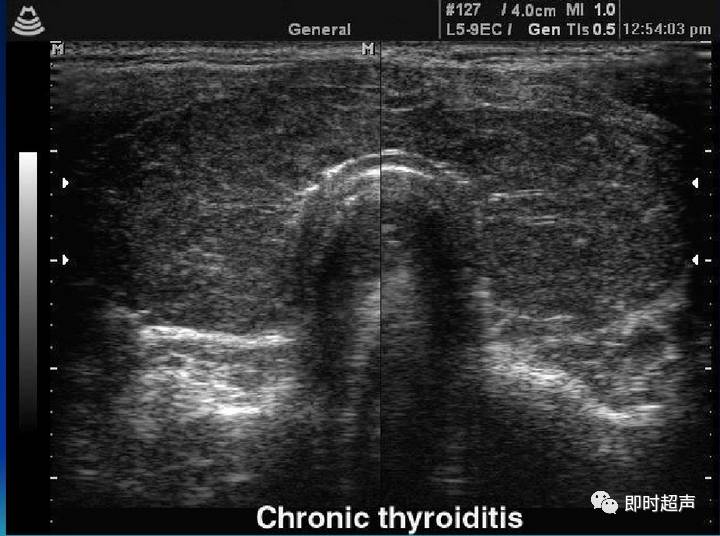

2015年第36卷第9期 云 南 中 医 中 药 杂 志 9 刘铜华教授治疗桥本 氏 甲状腺炎 的临床 经验 邓 莉 ,刘铜华 ,孙 文 (1.陕西中医学院,陕西 咸阳 712000;2.北京中医药大学,北京 100029) 摘要 : 目前 国内外对桥本氏甲状腺炎治疗尚缺乏统一认识 ,导师刘铜华教授认为其致病原 因多样 ,关键在 于情志 内伤 ,总属本虚标实,致病 因素责之 气滞、痰凝 、血瘀 ,后期 气阴两虚。治疗 中应重在理 气解郁 ,调 畅情 志 ;软 坚散 结;同时注意顾护阴液,存正气。临床诊 断与治疗过程 中,以中西医相 结合的方式扩 大诊 疗范围,有 助于对病情的监控 ,及时调整用药。 关键词 :桥本 氏甲状腺 炎;刘铜华;临床经验 中图分类号 :R265 文献标志码 :A 文章编号:1007—2349(2015)09—0009—03 桥本 甲状腺炎 (Hashimoto thyroiditis,HT)又称为 慢性淋 巴细胞性 甲状腺炎 (CLT),是一种常见的 自身 免疫性 甲状腺 疾病。本病 多见于 中年 女性 ,起 病 隐 匿,病程较长。主要表现为 甲状腺弥漫性肿大 ,质地 坚韧,多无明显症状 ,疼痛少见。